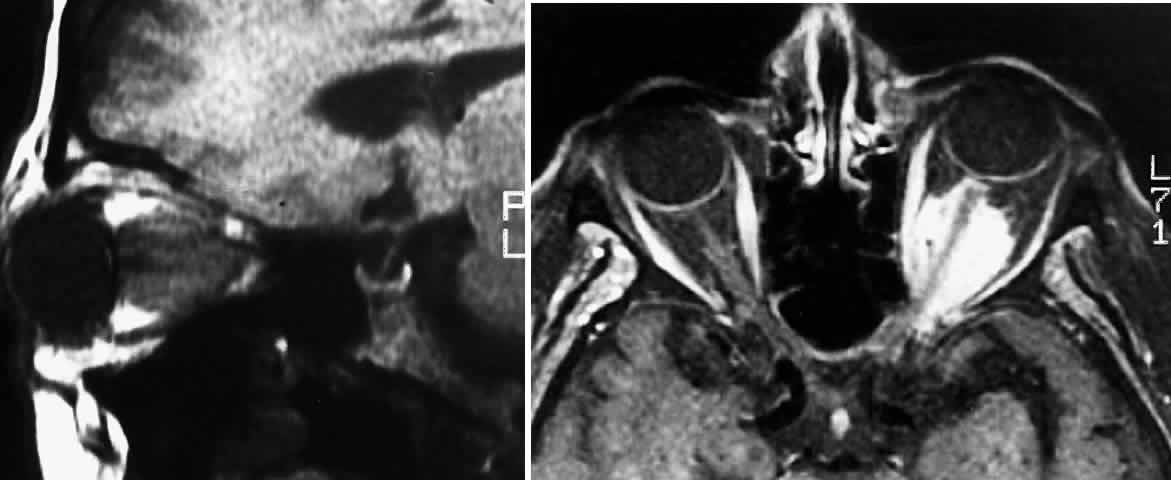

Globular tumors in the suprasellar area that lack these features usually require craniotomy and biopsy confirmation. Lesions that may be difficult to distinguish from optic pathway gliomas include germinomas of the visual system and optic nerve choristoma because they both may appear intrinsic to the visual pathway.13 Tumors such as craniopharyngiomas and pituitary adenomas usually do not appear intrinsic to the visual pathway and may have features of sellar enlargement. Findings such as enhancement of the leptomeninges or peripheral enhancement of an enlarged chiasm are atypical of optic glioma and may indicate an inflammatory process masquerading as a glioma.83 Aneurysms in the suprasellar area may sometimes appear on neuroimaging to be intrinsic to the visual pathway. Better definition may be noted with magnetic resonance angiography.13 In contrast to orbital optic nerve gliomas, meningiomas enhance strongly with gadolinium and are less common in children. Meningiomas have the following features on axial CT scanning that are not typically shared by optic nerve gliomas:

5. Calcification84 (Fig. 5 A and B)

Fig. 5. A. T1-weighted oblique MRI of the orbit, demonstrating an optic nerve glioma. B. Contrast-enhanced T1-weighted axial MRI of the orbit, demonstrating left meningioma with intracanalicular extension.